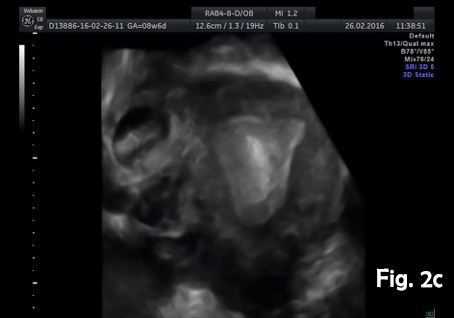

A 39-year-old woman presented for a routine dating scan at 8 weeks 6 days amenorrhea. At examination she also was asymptomatic. Ultrasound examination revealed an empty uterine cavity with a regular endometrium and a gestational sac with a viable embryo located in the interstitial portion of the right fallopian tubes, separate and greater than 1 cm from the lateral edge of the uterine cavity (Fig.2a). The sac was surrounded by a thin myometrial mantle (Fig.2b). Color Doppler sonography revealed peritrophoblastic blood flow around the gestational sac and heart movements (Video 1). No fluid was seen in the pouch of Douglas. Bulging of the outer contour of the uterus in the cornual region was shown on 3D ultrasound (Fig.2c). Laparotomy with excision of the interstitial portion of fallopian tube and right cornual part of the uterus was performed. The postoperative period was uncomplicated.

3D ultrasound facilitates the visualization of the interstitial portion of the tube, due to its capability to image the coronal plane of the uterus and may be helpful in differentiating between intrauterine and interstitial pregnancies in difficult cases [14].

Figure 2c. 3D ultrasound (coronal view). Eccentrically located gestational sac outside the endometrium and surrounded by myometrium. Bulging of the outer contour of the uterus in the cornual region.